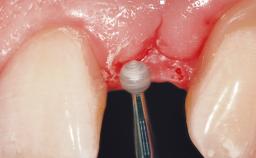

| Placement Protocol | Immediate implant placement |

| Socket Morphology | Single-root socket |

| Socket Integrity | Damage to one or more bone walls |